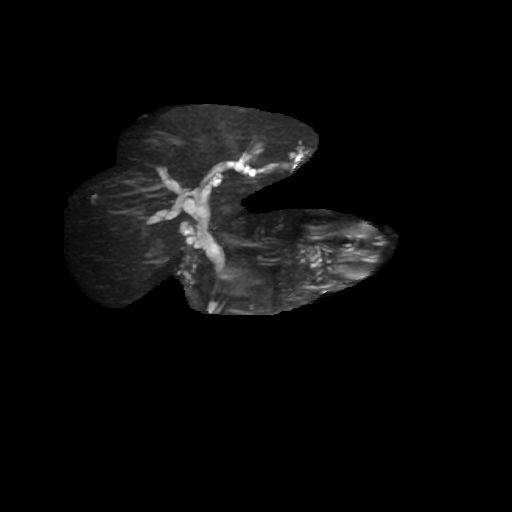

门诊MRCP :胰管与胆总管交界处小囊样扩张,约0.5X0.6厘米,先天变异可能。胆囊管残端较长。肝内外胆管及胰管未见明显扩张。